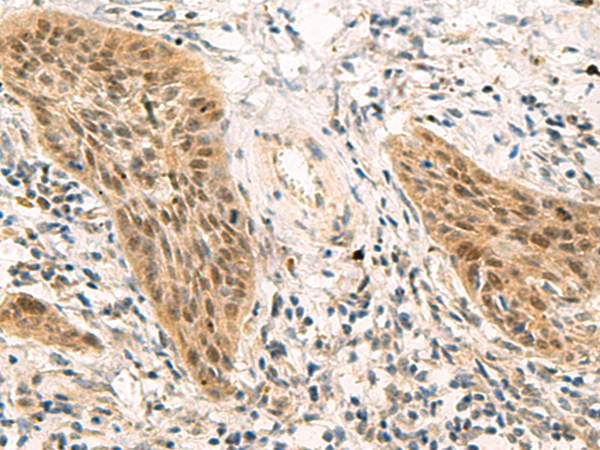

IHC positive control: |

Human esophagus cancer |

IHC Recommend dilution: |

50-200 |